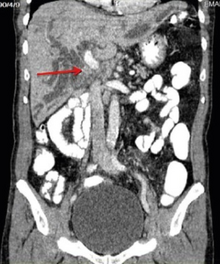

Klatskin tumor, also known as hilar cholangiocarcinoma, is a type of cancer of the biliary tree (cholangiocarcinoma) occurring where the right and left bile ducts join.

The ultrasonography (and the use of Doppler modes) permit definitive diagnosis of a large number of lesions and the involvement of hepatic hilum,[12] but it is less sensitive than CT or MRI in detecting focal lesions.[13][14]

Ultrasonography always detects dilatation of the bile ducts, but more rarely the tumor itself.[15]

Magnetic resonance cholangiopancreatography (MRCP) is a good non-invasive alternative to these other procedure. This technique demonstrates hepatic parenchyma and it's accurate for detecting nodular carcinomas and infiltrating lesions.[16]